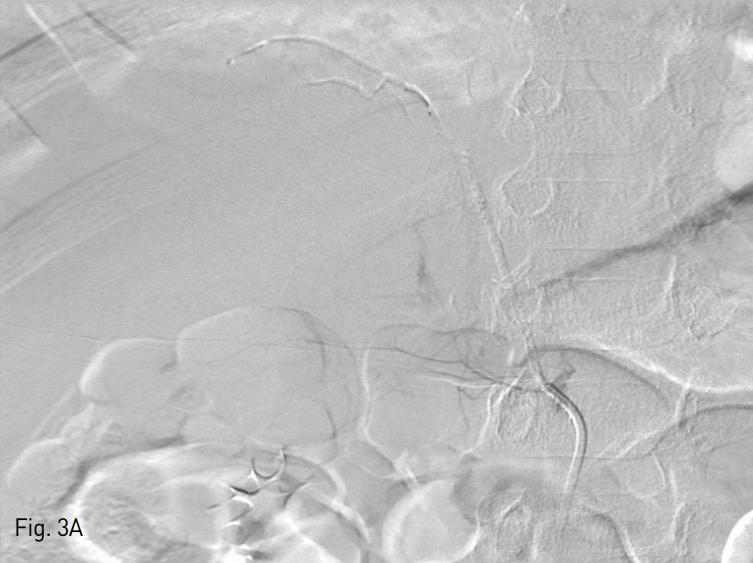

이후 4Fr cobra catheter를 통한 추적 오른쪽 아래가로막동맥조영술에서 상, 중 부신동맥에 대한 색전은 잘 확인되나, 하 부신동맥을 통한 혈류 흐름이 확인되었다 (Fig. 3A). 이에 하 부신동맥에 대한 보다 자세한 평가를 위해 microcatheter를 사용하여 하 부신동맥을 초 선택하였고, 선택적 조영술 상에서 오른쪽 부신의 하부 실질이 확인되나, 활동성 출혈이 있는지 여부는 확실히 배제할 수 없었다. 이에 Gelfoam (Alicon, Zhejiang, China)을 이용하여 색전을 시행하였다. 그러나 시술 과정 중 작은 가성동맥류가 확인되어 (Fig. 3B), NBCA와 Lipiodol 혼합물을 사용하여 추가 색전술을 시행하였다. 이후 추적 오른쪽 아래가로막동맥조영술에서 혈관 외 유출이 없음을 확인하고 시술을 종료하였다 (Fig. 4).

Fig. 3

A. After embolization of theright superior and middle adrenal arteries, follow up RPIA arteriogram shows intact right inferior adrenal artery. And we couldn' t exclude the possibility of the active bleeding of right inferior adrenal artery. So we took preven tive embolization about the right inferior adrenal gland with gelfoam.